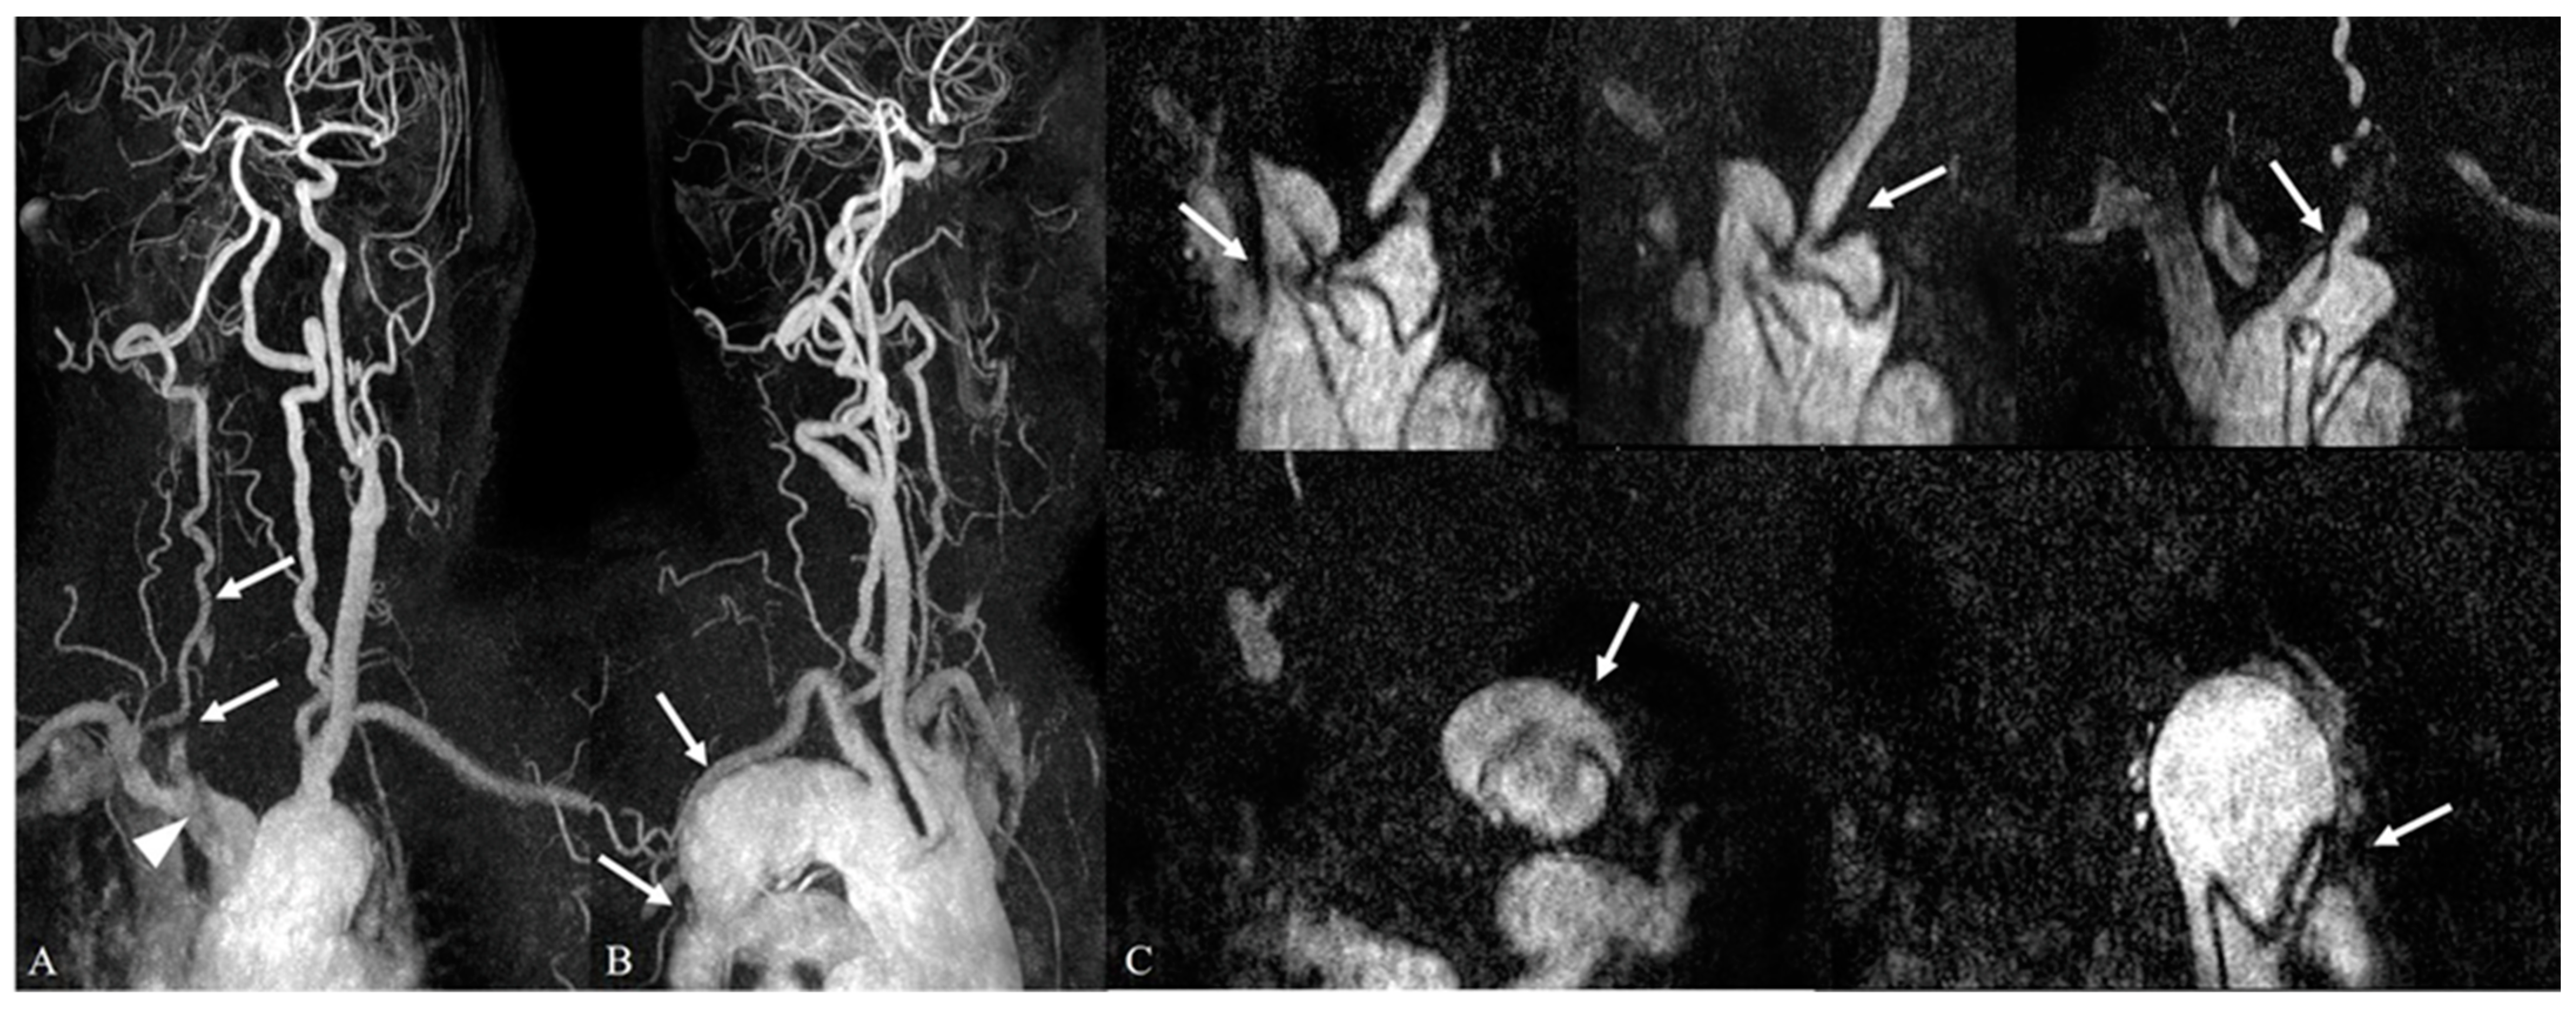

3.3. Intracranial and Extracranial Arterial Abnormalities beyond the Aortic Arch on Contrast-Enhanced Neck MR Angiography

| Arterial Abnormalities | Intracranial Abnormality (250/348, 71.8%) | Extracranial Abnormality (136/348, 39%) |

| Category I (Clinically significant findings) | 130/250 (52.0%) | 38/136 (27.9%) |

| Severe stenosis | 37/250 (14.8%) | 23/136 (16.9%) |

| Occlusion | 23/250 (9.2%) | 10/136 (7.4%) |

| Aneurysm | 66/250 (26.4%) | 5/136 (3.7%) |

| Arteriovenous malformation | 4/250 (1.6%) | NA |

| Category II (Minor or no significant findings) | 232/250 (92.8%) | 112/136 (82.4%) |

| Mild to moderate stenosis | 106/250 (42.4%) | 94/136 (69.1%) |

| Penetrating atherosclerotic ulcer | 18/250 (7.2%) | 8/136 (5.9%) |

| Junctional dilatation | 17/250 (6.8%) | 2/136 (1.5%) |

| Congenital anomaly | 75/250 (30%) | 7/136 (5.1%) |

| Stent placement | 16/250 (6.4%) | 1/136 (0.7%) |